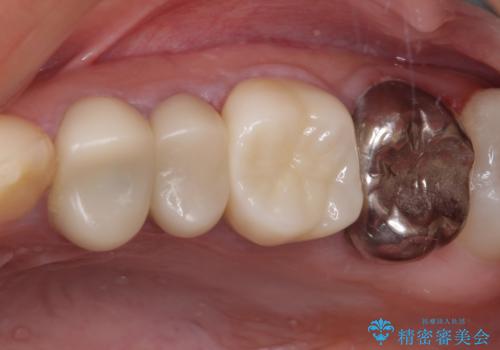

- 笑ったときに見てしまう上顎奥歯の銀歯を気にして来院された患者様です。

折角セラミッククラウンを装着するので、根管治療を行った後に補綴治療を行うこととしました。

他にも目立つ銀歯がありましたが、最も気にしている2本を優先して行うこととしました。

結婚式前にはクリーニングやホワイトニングを行い、その後他の歯を治療していく予定です。